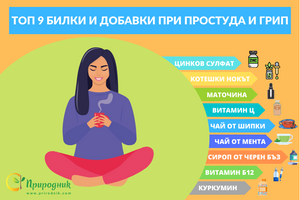

Съвети при настинка и грип

от Aneliya Dikova • 15 мин. четенеКога за последен път сте имали симптоми на настинка или грип? Някои хора се заразяват с грипен вирус всяка година или няколко пъти годишно. Независимо дали става въпрос за възпалено гърло, инфекция на синусите, бронхит или пневмония, грипният вирус може да предизвика множество нежелани и дори животозастрашаващи симптоми и състояния. В тази статия ще научите как да си помогнете за предотвратяването на грипа, кои хранителни добавки и храни да включите в диетата си и какви мерки можете да предприемете, за да се излекувате ако сте се разболели от грип. -